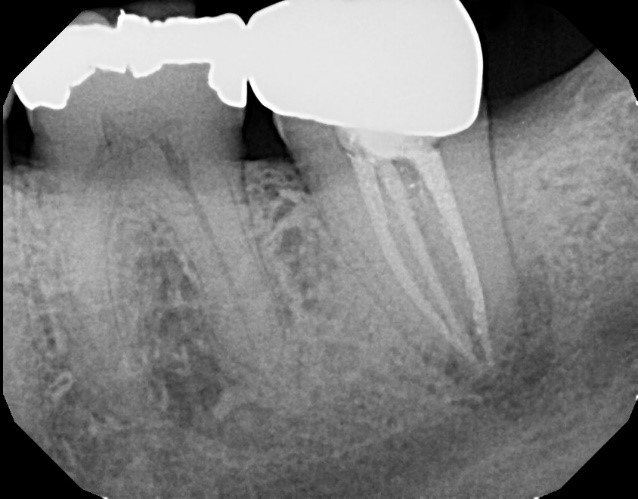

Here is a case in point: A long-term patient with an endodontically treated molar managed with a clinically acceptable crown presents with a new periapical asymptomatic lesion (Fig. 3). The diagnosis, based on radiographic and clinical history, is a recurrent periapical abscess due to microleakage. The tooth is adequately re-treated by a skilled endodontist and restored.

Less than 12 months later, the tooth develops a localized distal 9 mm periodontal pocket with bleeding on probing (Fig. 4). Upon extraction of the tooth, the diagnosis of a vertical distal root fracture is confirmed by direct observation under magnification. Therefore, it’s important to consider the possibility of occult root fractures being present whenever restorative dentistry is planned.

suggests a vertical fracture, combined with a localized 9 mm periodontal pocket.